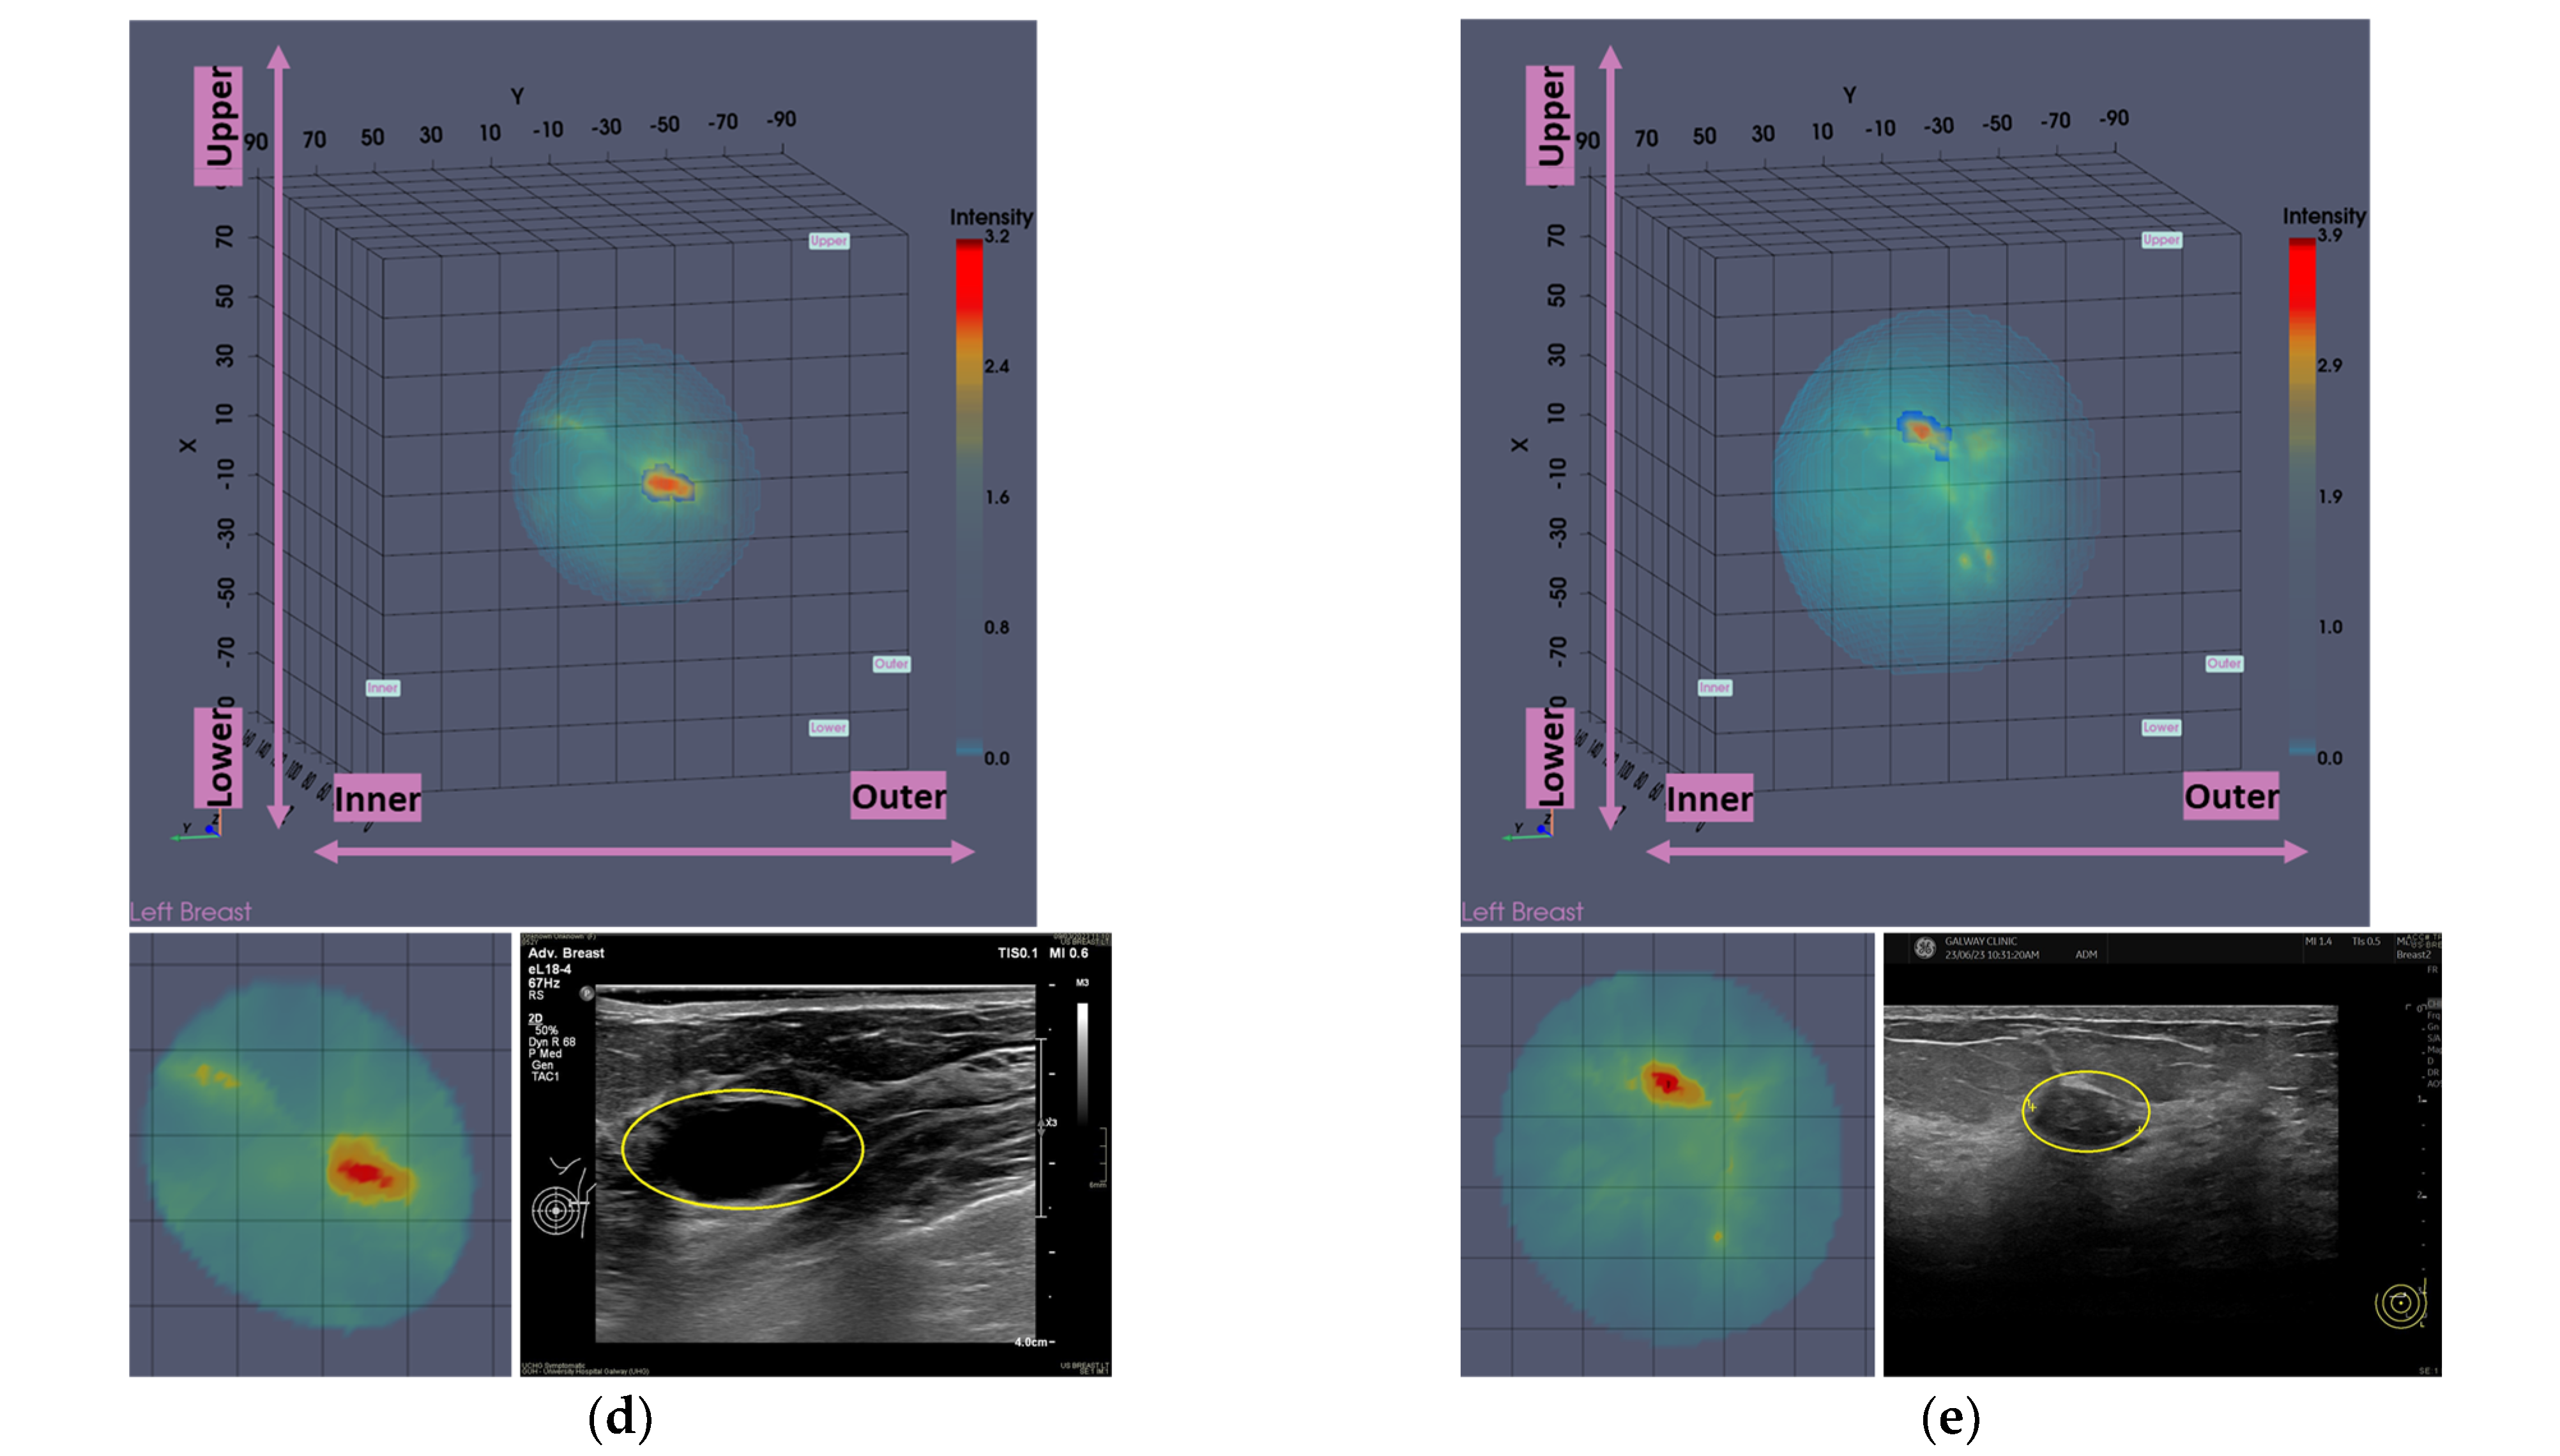

In Figure 1, the layout of the Wavelia#2 MWBI 3D imaging results is depicted, in addition to the reference imaging and clinical data for an illustrative study case with an Invasive Ductal Carcinoma at 12 o’clock in the left breast (Patient 003, Left breast scan—P003-L).

As part of the Wavelia MWBI scan data processing, the external envelope of the pendulous breast during the MWBI scan is first reconstructed and used to define the border of the two-propagation media: ‘in-breast’ and ‘out-of-breast’ in the MWBI imaging algorithm [44]. The quality of the MWBI-based breast contour reconstruction is highly important for the quality of the MWBI images, and it also serves to define the shape and size of the breast when inserted in the MWBI scanner. The methodological evolutions of the breast contour extraction module that were designed and implemented for the Wavelia#2 clinical investigation were recently presented in [44]. In Figure 1b, the external surface of the estimated full scanned volume is depicted in light gray color and superimposed with the Sagittal View of the 3D volumetric MWBI image while applying partial transparency.

The low-permittivity and high-permittivity images for this breast are depicted in the bottom row of Figure 1b. While the Global Averaged image was systematically used for image analysis in this clinical investigation, the low-permittivity representation contains a cleaner and more focused Region-Of-Interest (ROI) associated with the IDC in the case of this breast.

In Figure 2, the layout of the Wavelia MWBI 3D volumetric breast image analysis packaged output is illustrated for the same study case (P003, IDC at 12 o’clock position of the left breast).

The Wavelia MWBI scan image analysis output includes (a) the set of extracted ROIs localized with reference to the reconstructed external surface of the breast, (b) image quality metrics assessment (Signal-to-Noise Ratio (SNR) and Contrast-to-Noise Ratio (CNR)), (c) ROI size estimation: maximal linear dimension [mm], and (d) radiomic feature computation for ROI characterization: shape descriptors, 1st-order statistics of ROI intensity, Gray-Level Co-occurrence Matrix (GLCM) texture, and Neighbor Gray-Tone Difference Matrix (NGTDM) texture metrics.

Good correspondence between the morphology and maximal linear dimension of the extracted ROIs from the Wavelia MWBI volumetric images and the ultrasound reference representations of the lesions is notable by comparative visual inspection of the images in Figure 9c–e. The case in Figure 9b is the same case used in Section 2 to illustrate the layout of the Wavelia MWBI imaging and image analysis outputs in Figure 1 and Figure 2, respectively. Based on the more detailed clinical reference information provided for this case in Figure 1a, there is clear evidence that the ultrasound scan provided only partial visibility of this IDC, resulting in a severe underestimation of its size in this case. The 19 mm size of the excised tumor, as per the post-surgery histology report, also considering that the patient underwent neoadjuvant chemotherapy before surgery and after the Wavelia MWBI scan of the breast, renders the MWBI-based estimate of the lesion size relevant and worth highlighting in this case.